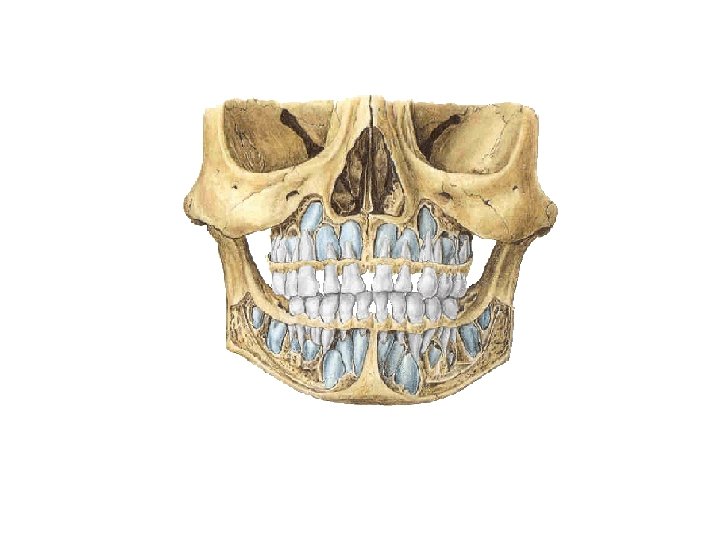

牙Teeth General features • Two sets: – 乳牙Deciduous – 恒牙Permanent • Classification: – – 切牙Incisors 尖牙Canine 前磨牙Premolars 磨牙Molars

Deciduous teeth: are 20 in number • Ten teeth in each mandibular and maxillary arch • Central incisor中切牙, lateral incisor侧切牙, canine尖牙, first molar第一磨牙 and second molar第二磨牙 in each quadrant Upper jaw Lower jaw Ⅰ in. Ⅱ Ⅲ Ⅳ Ⅴ total 20 in. can. mol. • Eruption: stars at about 6 mouth of age and continues to beginning of 3 rd year • Shedding: occurs between 6 th and 12 th years with replacement by permanent teeth

Permanent teeth (adult): are 32 in number • Sixteen in each mandibular and maxillary arch • Two incisors, one canine, two premolars, and three molars in each quadrant Upper jaw 1 2 3 4 5 6 7 8 total 32 Lower jaw • First permanent molar- appears at about 6 years • Third molars (wisdom teeth)-many erupt at any time after 12 years of age or not at all (impaction).